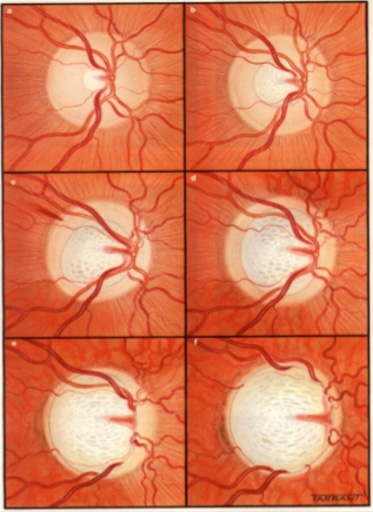

The change in the optic nerve head as a result of high IOP is called cupping. The optic nerve head changes shape with the central portion enlarging and bending backwards.

As the damage to the optic nerve continues, the eye will develop visual field loss. Certain patterns of visual field loss are characteristic of glaucoma and will continue to worsen if the disease progresses. Visual field testing is a fundamental part of glaucoma management.

As the cupping increases, the axons of the optic nerve become damaged, causing the retinal ganglion cells to die. The fibers of axons make up the nerve fiber layer of the retina. As glaucoma worsens the nerve fiber layers thins. The thinning of the nerve fiber layer and cupping of the optic nerve head can be measured and monitored very precisely with specialized diagnostic testing, called OCT (Optical Coherence Tomography).

Optic Nerve Head appearance in a normal eye (A)

and an eye with glaucoma (B)